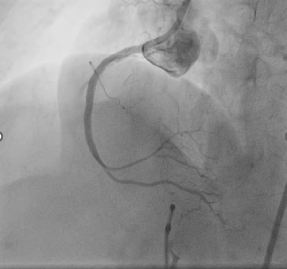

Post rotational atherectomyangiogram and IVUS run taken

In view of 300-360 degrees ofcalcium arc and not good MLAs in mid and proximal RCA post ROTA we decided todo Intravascular lithotripsyIntravascular lithotripsy with 3.0x12mm balloon done in mid and proximal RCA

DES 2.75x28 deployed in mid-distalRCA

DES 3.0x38 deployed in ostioproximal-midRCA

Post rotational atherectomyangiogram and IVUS run taken

In view of 300-360 degrees ofcalcium arc and not good MLAs in mid and proximal RCA post ROTA we decided todo Intravascular lithotripsyIntravascular lithotripsy with 3.0x12mm balloon done in mid and proximal RCA

DES 2.75x28 deployed in mid-distalRCA

DES 3.0x38 deployed in ostioproximal-midRCA